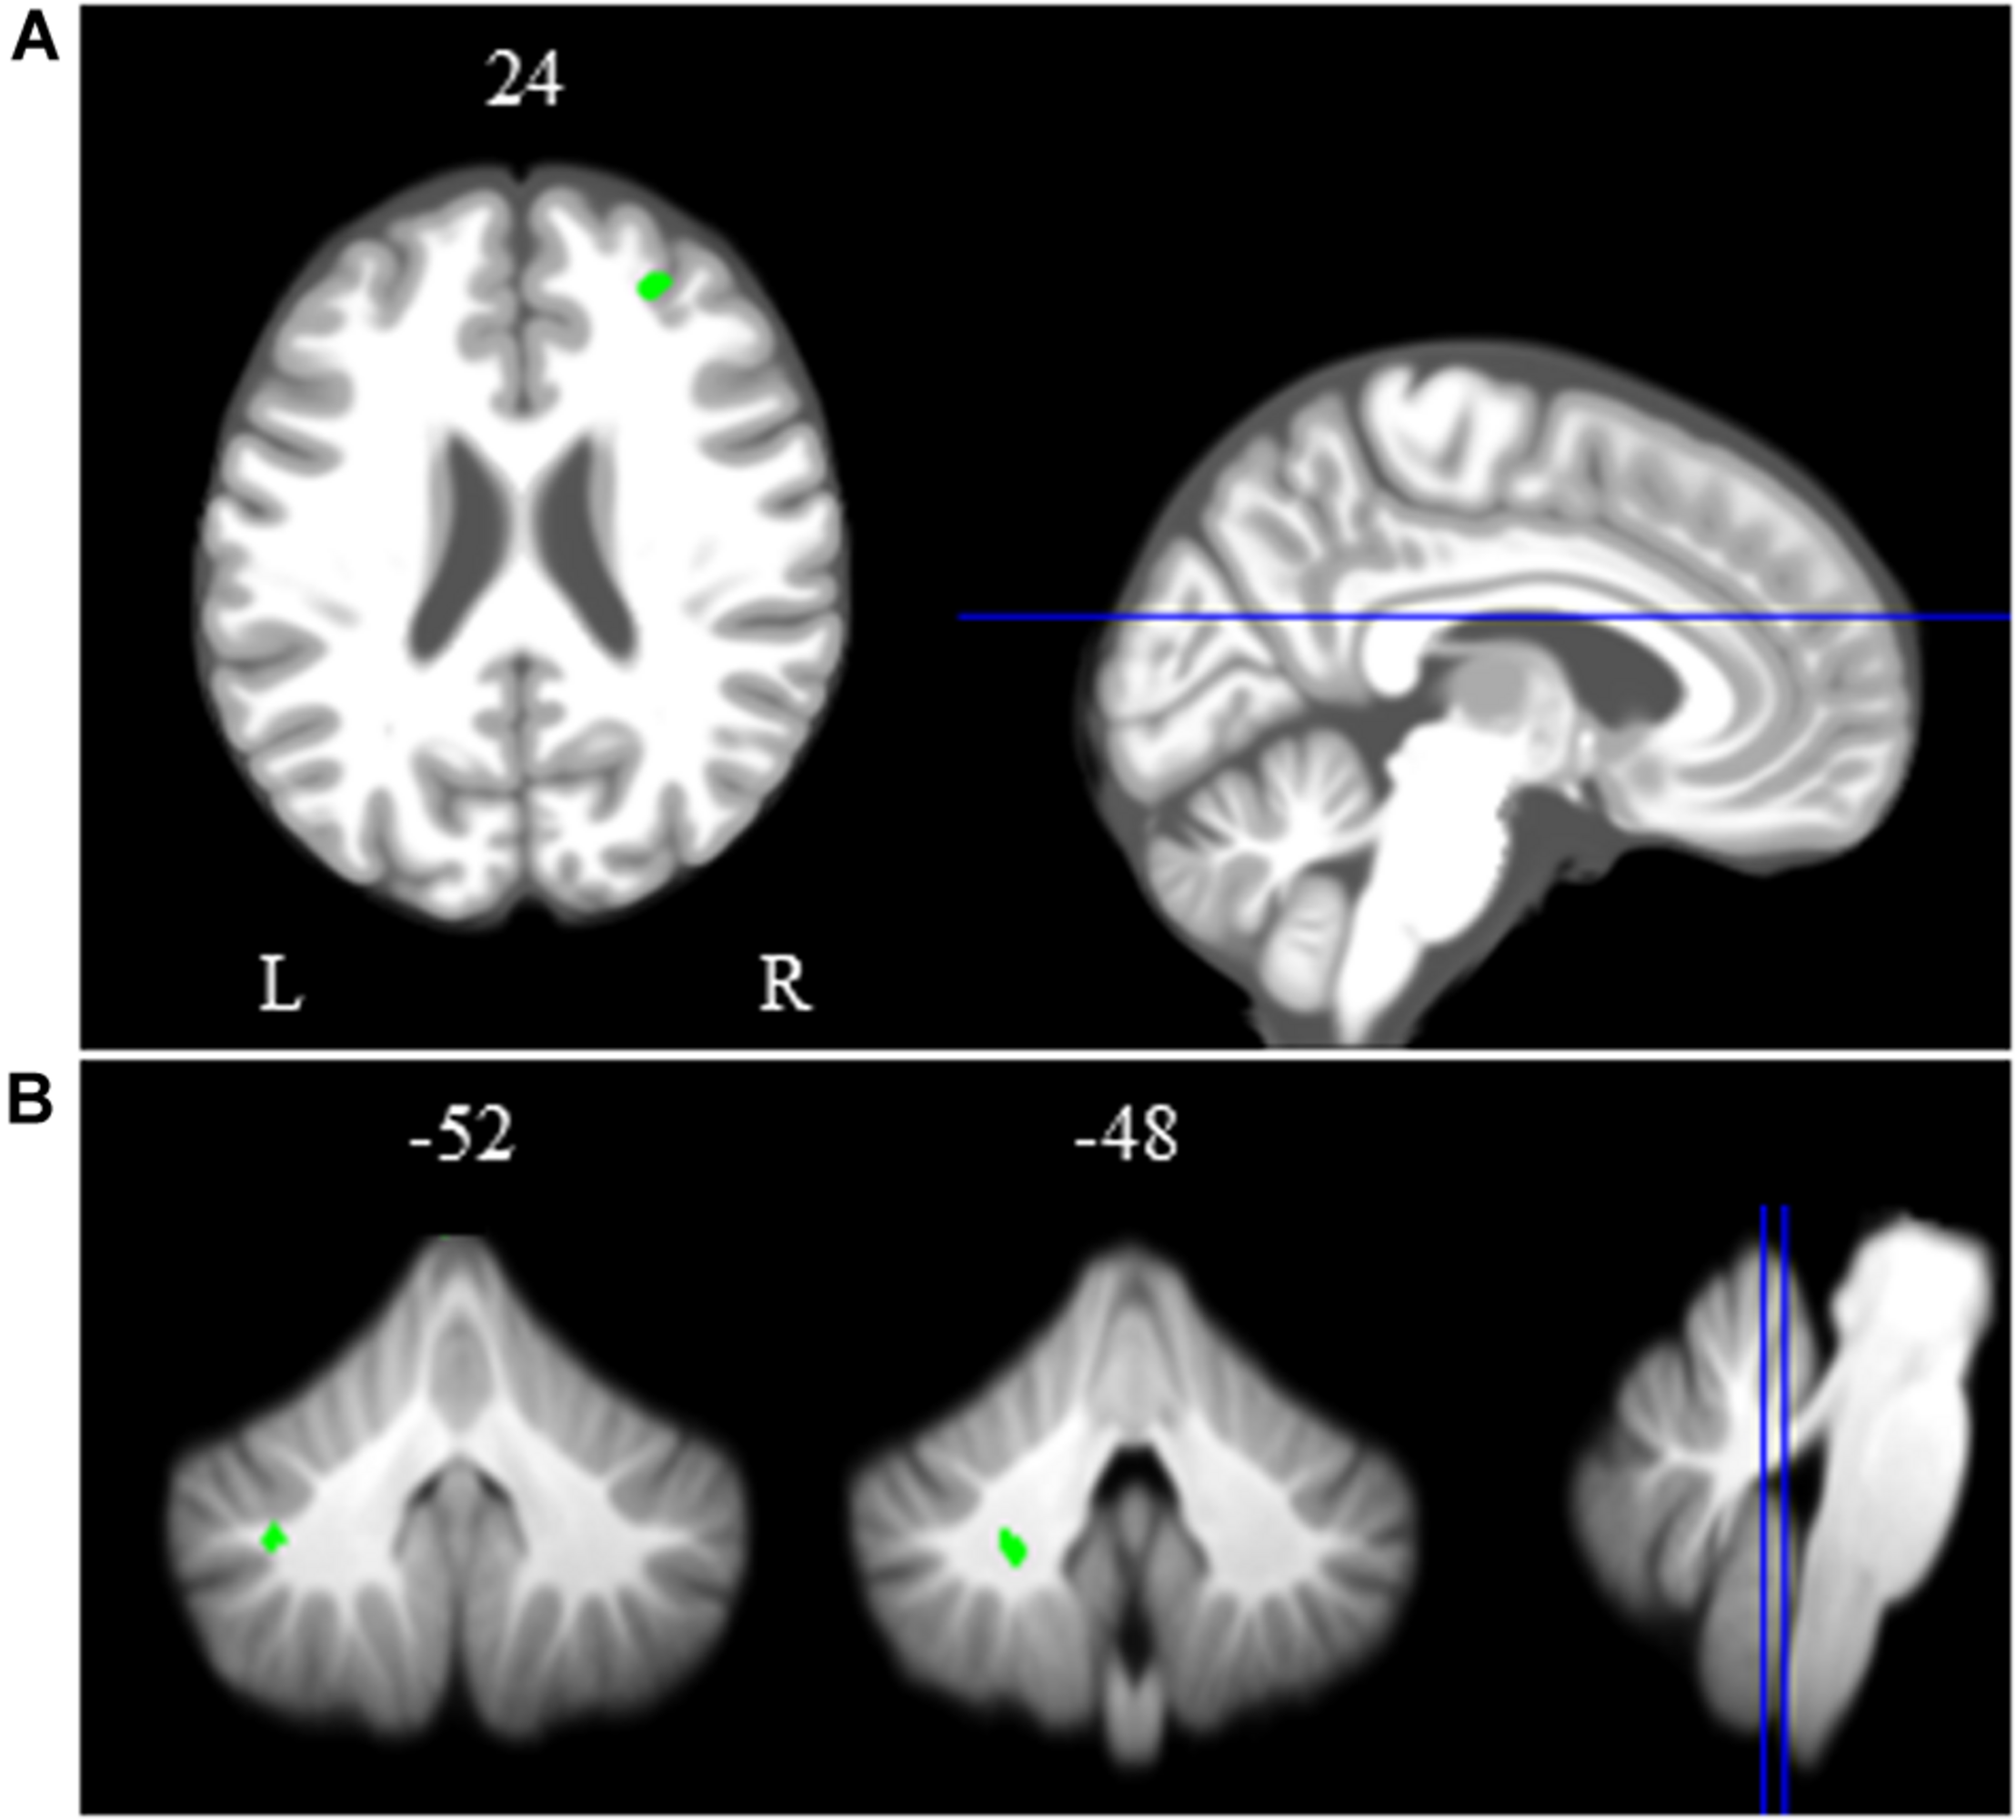

Brain-Behavior Correlations

Spatial Working Memory Task

We identified several regions for which the slope of change in brain activity correlated with the slope of change in spatial working memory performance (Figure 6A and Table 3). For instance, for spatial working memory accuracy, we observed that greater increases in activation of the right angular gyrus were associated with larger improvements in spatial working memory performance. That is, subjects who performed this task with fewer errors presented with greater increases in activation of the right angular gyrus during the HDBR + CO2 intervention. Further, a greater decrease in activation of the inferior frontal gyrus was correlated with less decline in spatial working memory accuracy. For the spatial working memory control task, we found that greater increases in activation of several brain regions, including parietal, temporal and occipital regions, correlated with greater accuracy increases. In addition, greater decrease in activation of the left lingual gyrus was correlated with less decline in the accuracy of the spatial working memory control task (Figure 6B and Table 3). Regarding the spatial working memory scores, we observed that greater increases in activation of the right superior temporal gyrus were correlated with greater increases in scores (Figure 6C and Table 3).

Figure 6. Brain-behavior correlations (spatial working memory). Slope of changes in brain and behavior results showing positive (red) and negative (green) correlations. (A) Spatial working memory; (B) spatial working memory control; and (C) spatial working memory score. Whole brain results are overlaid onto the MNI standard template; p < 0.0005, k = 10. Right side correlation plots include contrast values extracted from the peak coordinate inside an example cluster (indicated with red or green arrows) graphed against the slope of changes in behavior results. Abbreviations: L = Left; R = Right; SWM = Spatial working memory.

HDBR + CO2 vs. 70-day HDBR Group Comparisons

Between-group normalized slope comparisons for HDBR + CO2 and 70-day HDBR revealed differences in the right hippocampus and left inferior temporal gyrus (Table 4). That is, the HDBR + CO2 group showed greater decreases in activation in both brain regions across the intervention in comparison to HDBR alone. These results were detected at the conservative, corrected statistical threshold of FDR < 0.05 (Nichols and Hayasaka, 2003).

Table 4. Regions with differences in slope of change in brain activation during bed rest between HDBR + CO2 and HDBR.